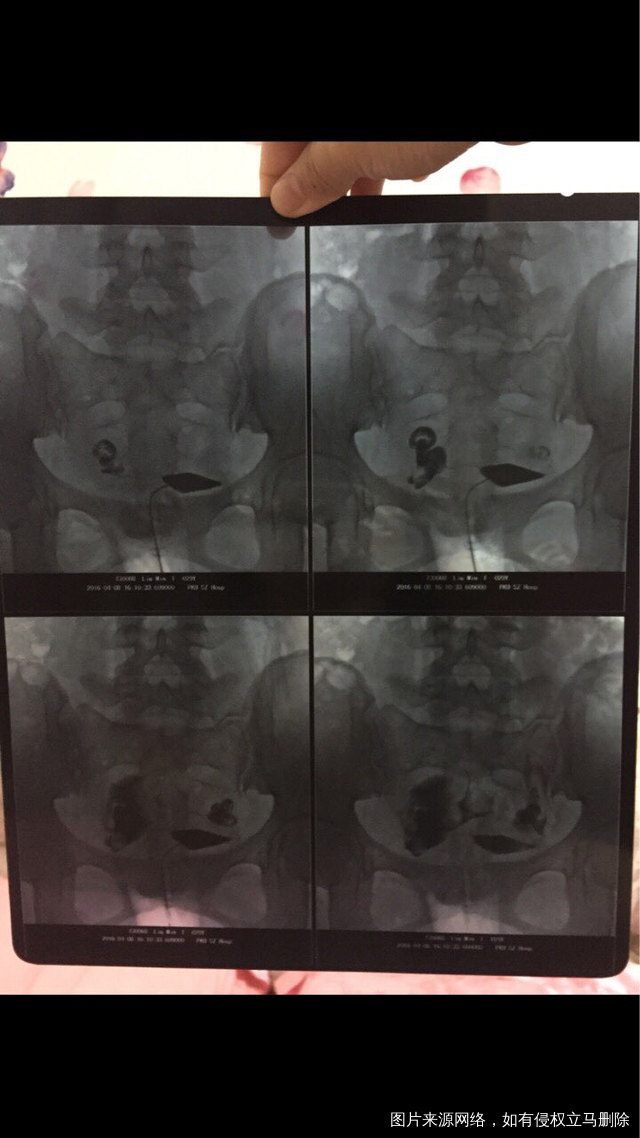

上面都是去年3⃣️月检查结果,我现在很迷茫不知道是做官还是试管,或者做别的治疗,医生我的输卵管通而不畅严重吗?备孕2⃣️年了,之前断断续续一直没怀孕,去年3月在医院做检查,试孕一年还是没怀了迷茫

上面都是去年3⃣️月检查结果,我现在很迷茫不知道是做官还是试管,或者做别的治疗,医生我的输卵管通而不畅严重吗?